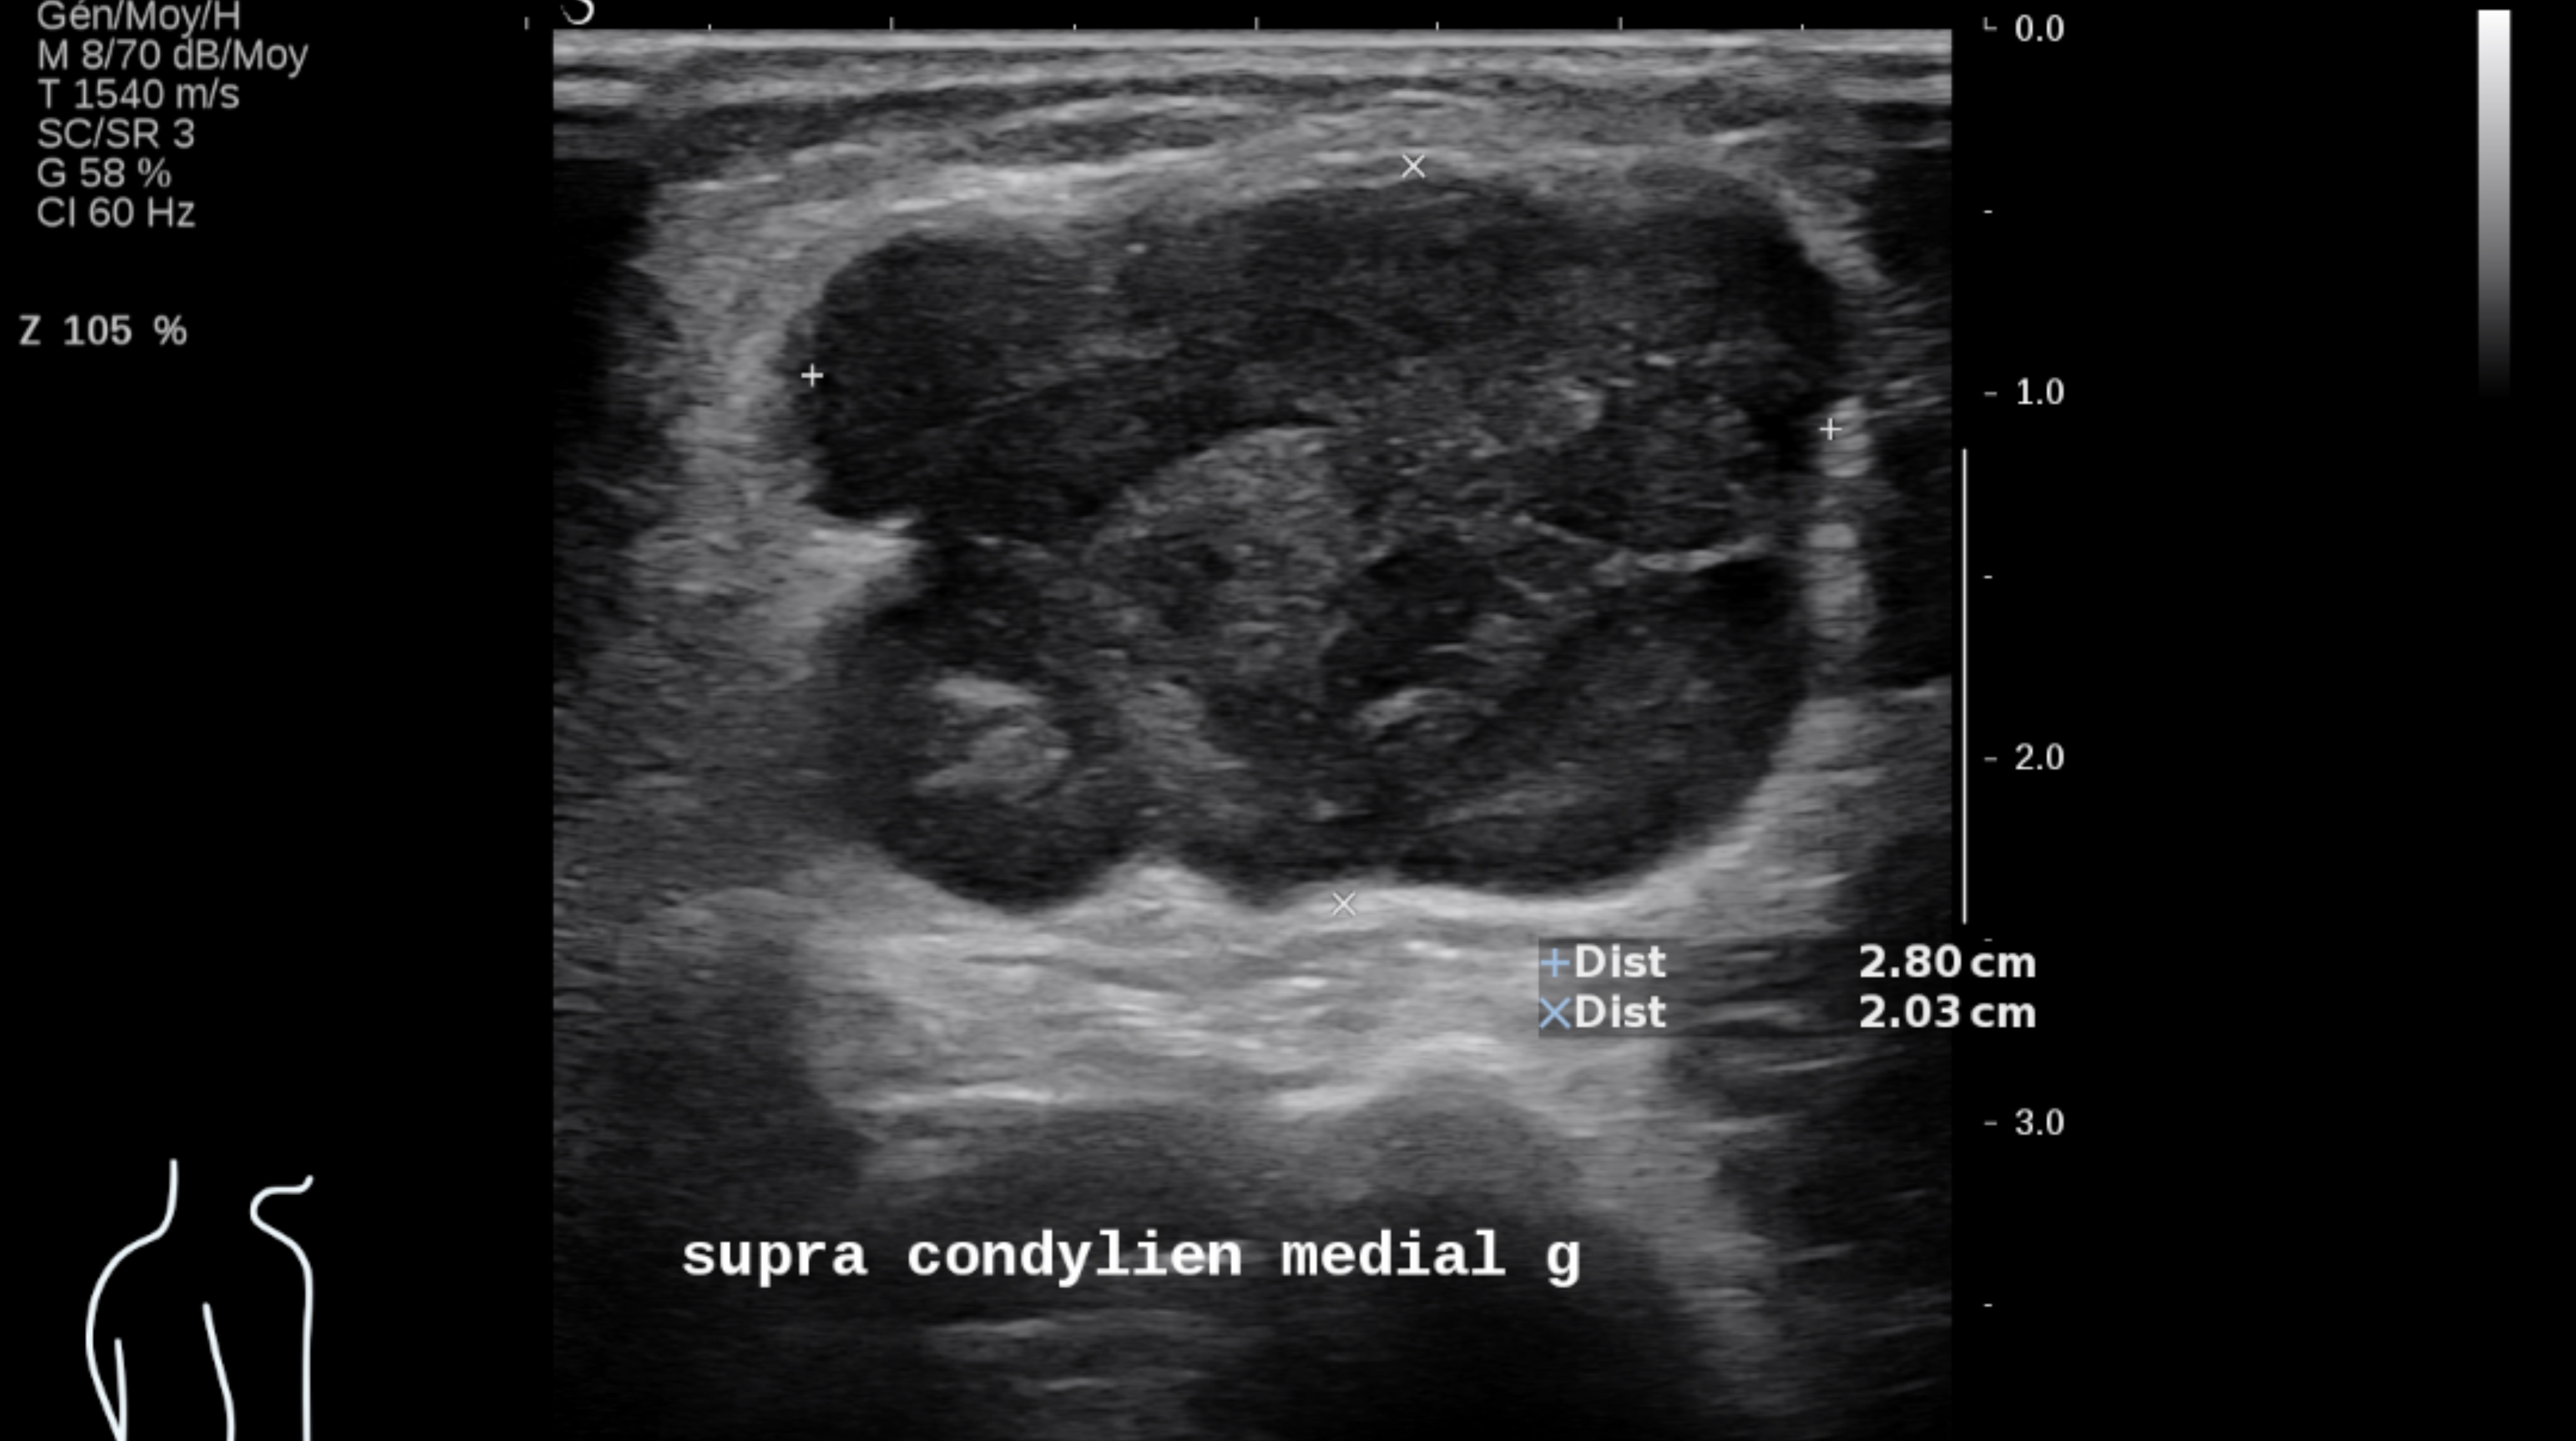

L’échographie reste le meilleur examen pour le suivi ganglionnaire superficiel et cutané des patients, à condition d’être réalisée par des opérateurs entraînés et spécialisés avec des appareils d’échographie performants utilisant des sondes de haute et très haute fréquence.